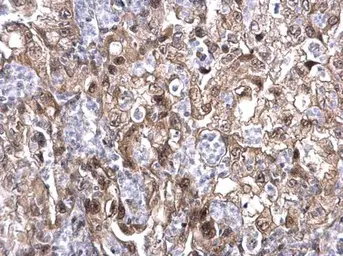

Anti-MAF1 antibody used in IHC (Paraffin sections) (IHC-P). GTX106776

GTX106776 IHC-P Image

MAF1 antibody detects MAF1 protein at nucleus and cytoplasm on human colon carcinoma by immunohistochemical analysis.

Sample: Paraffin-embedded colon carcinoma.

MAF1 antibody (GTX106776) dilution: 1:500.

Antigen Retrieval: Trilogy™ (EDTA based, pH 8.0) buffer, 15min